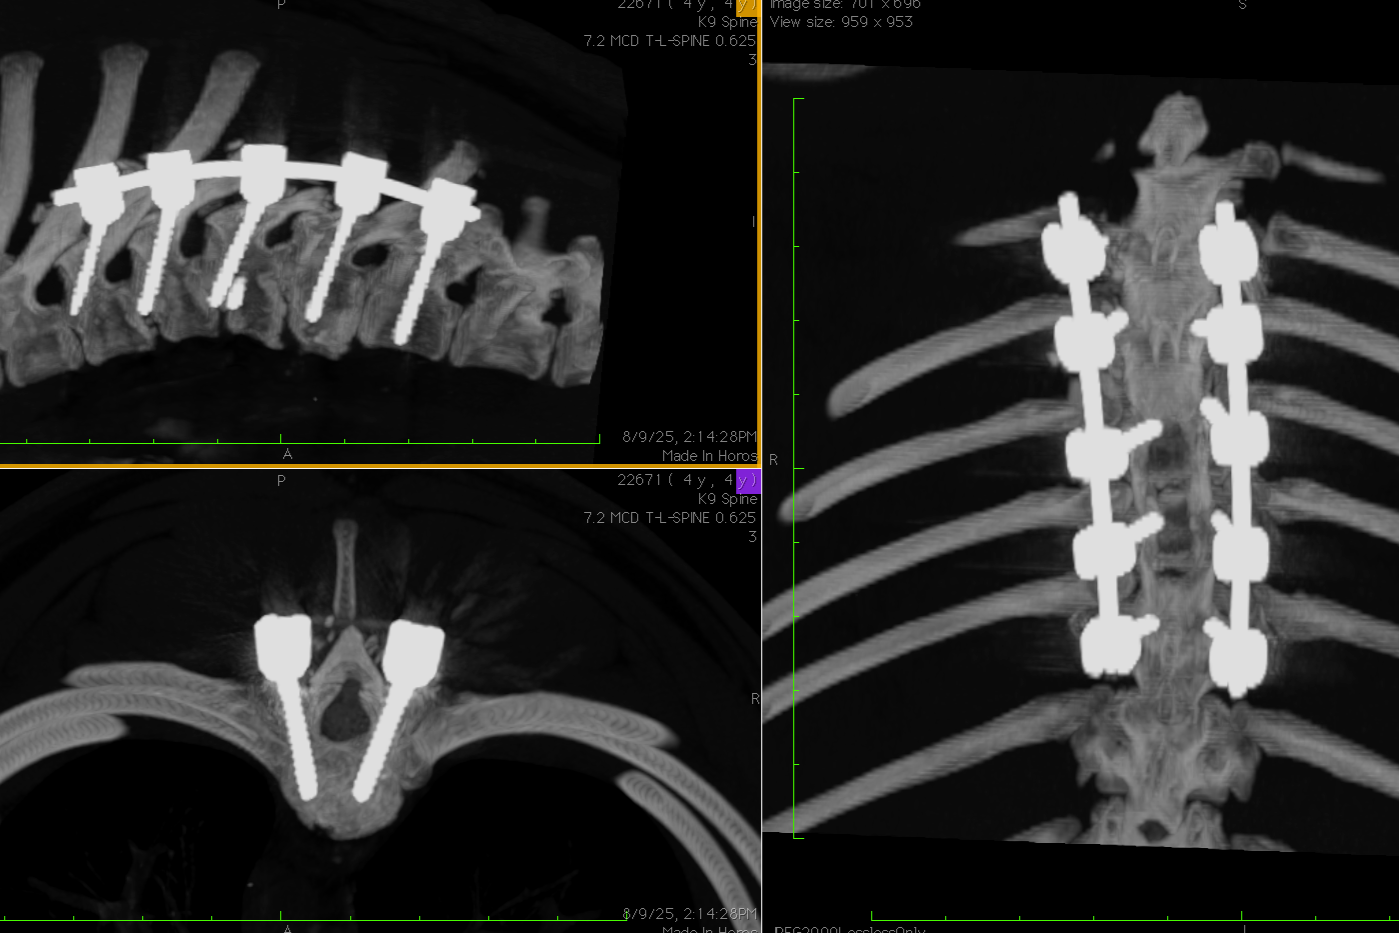

• Polyaxial screws available in 1.8mm, 2.2mm, 2.7mm and 3.2mm diameters in lengths from 7mm - 24mm.

• The tulip measures 6mm x 8mm with a 2.2mm titanium connecting rod and locking caps, torque limited to ensure the implant is tightened to exact engineered specifications. Frenchies and Pugs, ventral cervical stabilization… no problem.

The Bolt Mini is the smallest polyaxial screw available for veterinary patients. It is precision- engineered and made from human implant-grade titanium meeting the requirements of ASTM Standard F-136.

The Boreal Sciences Bolt Mini Spine System is the lowest profile small animal spine stabilization system available. Its ultra small stature is the result of a unique, state-of-the-art veterinary spine and human spine collaboration. Although the assembly is small, the Bolt Mini is designed to maximize the locking power and strength of the screw and rod construct.